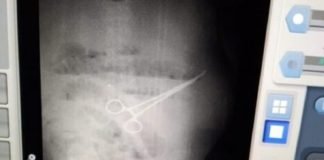

Fue sometido a una operación rutinaria en Maracaibo, le dejaron una...

Ocurrió en el Hospital Universitario de Maracaibo. Un paciente de 59 años fue sometido a una intervención quirúrgica de rutina, pero cinco días después...